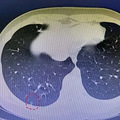

“要不是摔了那一跤,真是不知道會(huì)怎樣,想想都后怕。陳晨(化名)媽媽至今心有余悸。一次偶然的摔跤,竟查出自己才11歲的兒子患上肺癌,讓她怎么都想不到的是,這么小年紀(jì),兒子就和所謂的“成人癌扯上了關(guān)系。杭州市第一人民醫(yī)院心胸外科馮興副主任醫(yī)師說(shuō),...

早發(fā)現(xiàn)、早診治,早病愈?眼下,伴隨著大家對(duì)癌癥的恐慌,有一種很普遍的說(shuō)法,即癌癥不好治,主要是發(fā)現(xiàn)晚了,如果能早發(fā)現(xiàn),早治療,肯定能早治愈。據(jù)韓啟德院士介紹,近年來(lái),我國(guó)癌癥發(fā)病率顯著增高,2013年與1990年相比,癌癥新發(fā)病例數(shù)增加81%,其中肺癌由26.2萬(wàn)到...